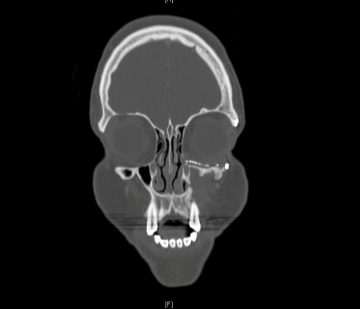

CT or MRI should be used when there is suspicion of traumatic, mechanical, or neoplastic obstruction. If there is suspicion for neoplasm, contrast is preferred, and scans should evaluate the lacrimal sac, orbit, and paranasal sinuses.

Dacryocystography is a radiographic procedure that involves dilating the lower punctum, inserting a small catheter, injecting contrast, and then imaging with x-ray or CT. Dacryocystography will visualize any blockage, trauma, inflammation, fistulas, diverticuli, tumors, or other anatomic abnormalities, but it does not differentiate well between the type of blockage. Due to modern imaging, dacryocystography is now rarely used.